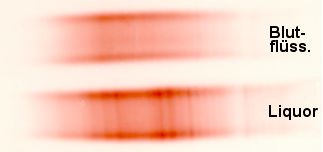

Eine andere Möglichkeit, eine Produktion im Liquorraum von einem einfachen

Übertritt aus dem Blut zu unterscheiden, ist die Auftrennung der Liquorimmunglobuline.

Sieht man dabei Immunglobuline vermehrt, die im Blut gar nicht vorkommen, dann spricht das

für eine Produktion im Liquorraum. Man macht dies mit Techniken, bei denen die

zusätzlichen Eiweißstoffe wie Streifen (Banden) auf dem Analysepapier erscheinen und

spricht daher auch von "oligoklonalen" Banden im Liquor, wenn man so etwas

findet.

Die zusätzlichen Banden (senkrechte Streifen) im

Liquor deuten auf eine Produktion von Immunglobulinen im Liquorraum hin. |